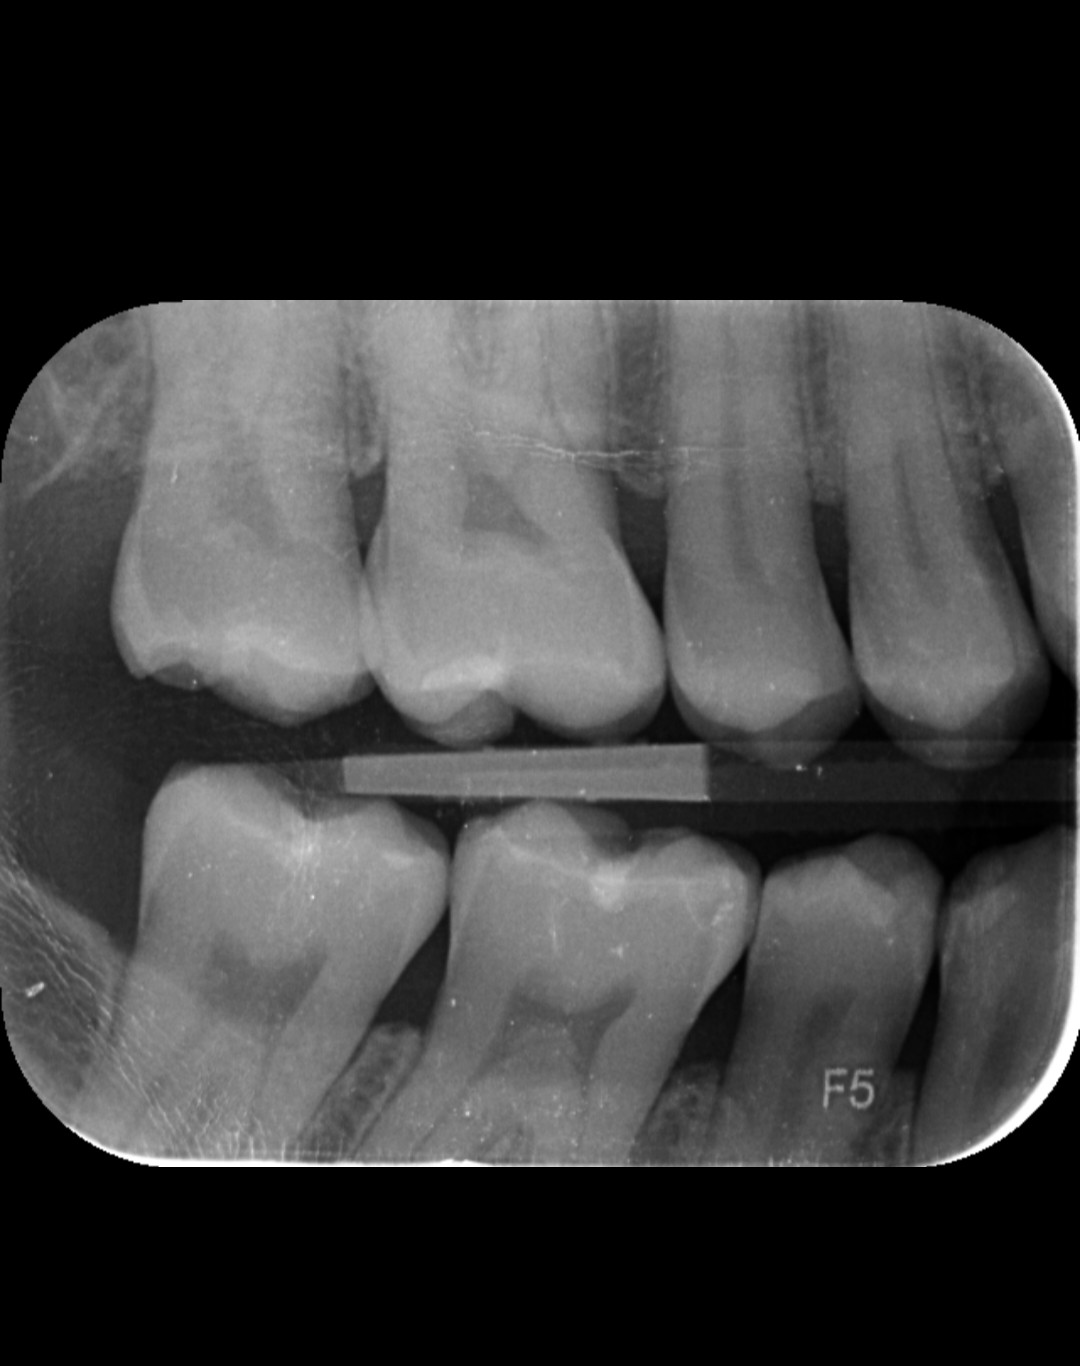

Ich habe wegen Umzugs den Zahnarzt gewechselt und seit vielen Jahren wieder mal ein Röntgen machen lassen. Ich hatte noch nie Karies. Am Schneidezahn vor dem Backenzahn unten links soll laut Zahnärztin Karies sein. Ich sehe nichts. Können Sie etwas erkennen? Vielen Dank für die Hilfe! MfG